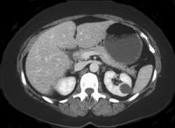

- 单项选择题女性,最近感腰部胀痛, 体检发现B超右肾正常,左肾有一囊肿, 双肾体积不增大,尿常规、肾功能正常, 无家族病史,CT表现如图所示, 最可能考虑为 ( )